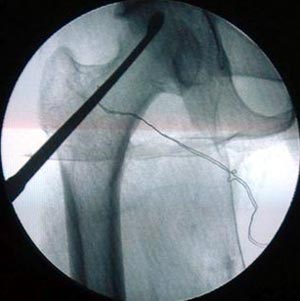

小切口髓芯减压

将患者的骨髓细胞特殊处理后复合骨生长因子和松质辜,异体或自体腓骨作为支撑物

患者35岁,双侧股骨头坏死。将患者的骨髓细胞与具有支撑力的植骨材料复合植入骨修复区。术后3年患者髋关节功能良好,无塌陷,无疼痛。